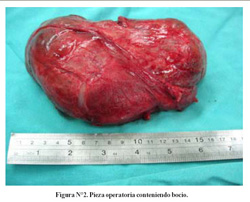

Una tomografía de tórax (Figura N°1) muestra que la tumoración cervical se extiende hasta el mediastino superior, con compresión y desviación de traquea cervical y torácica. Otros estudios rutinarios pre-operatorios de laboratorio fueron normales. Una biopsia por aspiración con aguja mostró ocasionales células foliculares tiroideas con presencia de material coloide. El paciente fue sometido a intervención quirúrgica iniciándose con una incisión cervical en collar, la cual luego se extendió inferiormente con una esternotomía mediana total. Se halló una tumoración gigante con origen en el lóbulo derecho tiroideo, anterior a la tráquea y al cayado aórtico; y posterior a la vena innominada. Se realizó una hemitiroidectomía derecha, en un tiempo de 4 horas 30 minutos, con un sangrado intraoperatorio de 1 500 mL, requiriendo transfusión de 3 paquetes globulares. El esternón se cerró con alambre y se colocaron dos tubos de tórax en el mediastino (32 French). El espécimen remitido medía 17 x 11 x 8 cm y pesaba 620 gramos (Figura N°2). El diagnóstico histopatológico final fue bocio coloide. El paciente tuvo evolución favorable, se retiraron los tubos de tórax en el día postoperatorio 5, saliendo de alta 9 días luego de la operación. La disfonía persistió, pero mejoro notoriamente a los 6 meses luego del alta. Un año mas tarde, el paciente continua en buen estado general sin evidencia de recurrencia de la lesión.